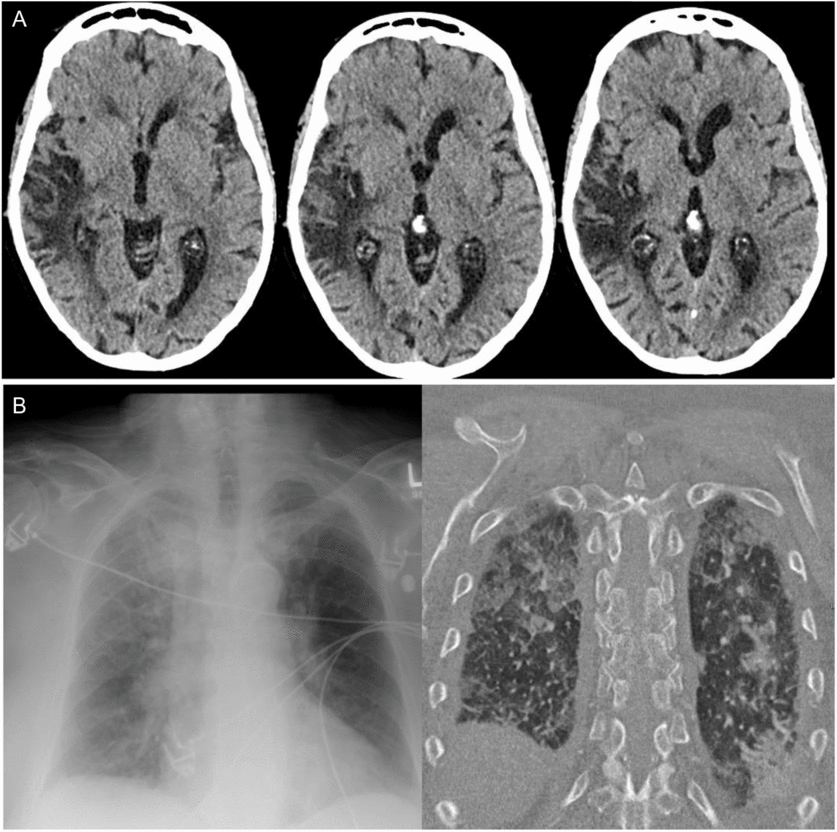

On arrival to hospital, there was persistent hypertension (246/121 mmHg), tachycardia, and tachypnea, and the patient was drowsy but alerted slightly to tactile stimulation. A non-contrast computed tomography (CT) scan of the head demonstrated right temporal-insular-parietal encephalomalacia consistent with the reported prior stroke (Figure 1A). She had a markedly elevated serum troponin, diffuse ST depression on electrocardiogram (ECG), acute kidney injury with hematuria and proteinuria, pulmonary edema (Figure 1B), and metabolic acidosis. After exclusion of aortic dissection, the patient’s hemodynamics were stabilized with diuresis and nitroglycerin infusion. This resulted in improvement in her level of consciousness within hours to near baseline, with some persistent slowing of verbal responses and retrograde amnesia for the preceding 24 hours. Despite overall improvement in awareness, in follow-up, the patient described having ongoing episodes of sensory experiences lasting seconds to minutes alternating between “shaved ice” and warmth descending from her pharynx to abdomen. It came to light that these sensory spells had been occurring less frequently for days to weeks prior to presentation, at times accompanied by negative thoughts.

Figure 1: Head and chest imaging at presentation. (A) Axial CT non-contrast head slices revealing previous infarct involving the superior temporal, posterior insular, and parietal lobes and (B) Chest x-ray and CT findings of bilateral alveolar infiltrates consistent with pulmonary edema.

We report a case highlighting the significant autonomic changes that can accompany temporal lobe seizures, through disruption of the CAN.Reference Baumgartner, Lurger and Leutmezer1, Reference Benarroch4, Reference Mraovitch and Calando5 Clinical studies suggest that these functions are lateralized with right hemispheric ictal activity accompanied by sympathetic excess (e.g. tachyarrhythmia, hypertension), whereas ictal bradyarrhythmia may be more common with left temporal seizures.Reference Baumgartner, Lurger and Leutmezer1, Reference Galli and Lombardi7–Reference Chouchou, Bouet, Pichot, Catenoix, Mauguiere and Jung9 An analogy and memory aid for the right hemisphere “go” and left hemisphere “slow” signal is the configuration of the gas pedal and brake pedal in a car. Additional features, as were present in our case include hypertension and “neurogenic pulmonary edema,” thought to be driven by sympathetic nervous system overactivation in acute central nervous system dysfunction.Reference Devinsky2 Although impossible to definitively rule out other causes of pulmonary edema, we suggest a neurogenic cause given the findings of acute dyspnea, tachypnea, and tachycardia in our patient, accompanied by chest x-ray imaging revealing alveolar opacities with a normal-sized heart, as well as echocardiogram revealing normal systolic ejection fraction. On review by cardiology, the ST segment changes on ECG were considered related to severe hypertension superimposed on coronary artery disease; however, ECG abnormalities can result from insular seizures; as well, cardiac type chest pain has been previously described in seizures involving limbic structures.Reference Baumgartner, Lurger and Leutmezer1, Reference Benarroch4 Urinary urge, as in our case, has previously been described in non-dominant temporal lobe seizures, with single photon emission computed tomography (SPECT) imaging highlighting hyperperfusion of the insula and superior temporal gyrus.Reference Devinsky2, Reference Baumgartner, Gröppel and Leutmezer10 The recurrent viscerosensory spells linked to negative thoughts, revealed in follow-up, coupled with the evidence of encephalomalacia of the posterior insula on CT scan (Figure 1A), suggest that our patient’s focal seizures may have started in the insula with propagation to medial temporal structures, resulting in dysautonomia and the restricted diffusion present on MRI (Figure 2).